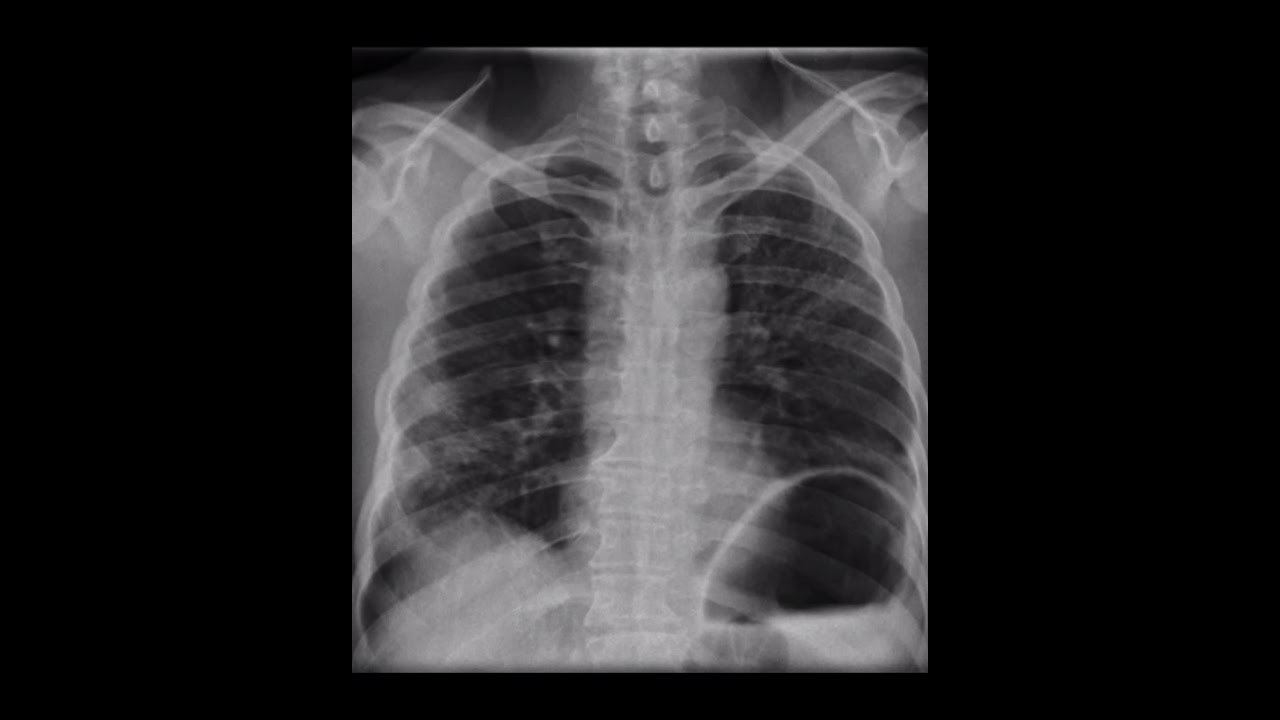

Veamos ⚠️🟡➡️ Elevación Hemidiafragmática ⚠️🟡➡️ popular

Actualmente - SEMINARIO :”SINDROME DE ELEVACIÓN DIAFRAGMÁTICA” Estudiantes VIII Semestre UPA. 23/11/2020. popular

La mayoría de las hernias diafragmáticas en adultos son asintomáticas y son hallazgos de exámenes de imágenes por otras causas. Su curso puede presentarse con molestias abdominales inespecíficas y rara vez debutan en forma aguda como consecuencia de una complicación.

Cursan la mayor parte de las veces de forma asintomática. En ocasiones requieren tratamiento quirúrgico.